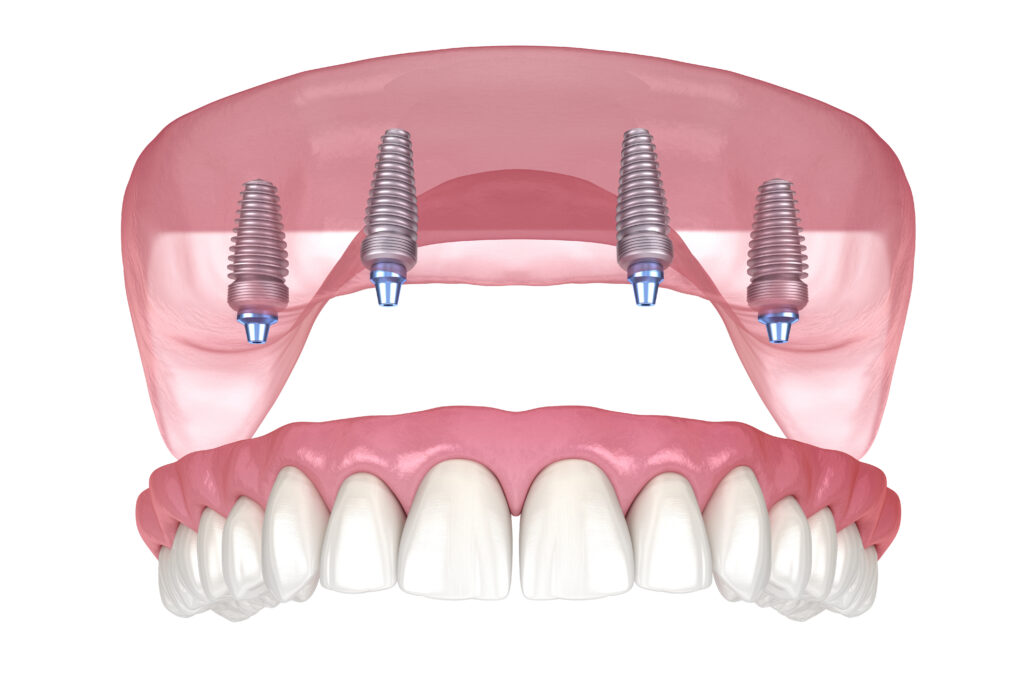

Dental implants are revolutionary components used to replace missing teeth. They consist of a titanium post that acts as a tooth root surgically placed into the bone. Over time, this post fuses with the bone through a process called osseointegration, creating a stable foundation for a replacement tooth. Once the post is securely anchored, a custom-made crown is attached, resulting in a natural-looking and fully functional tooth.